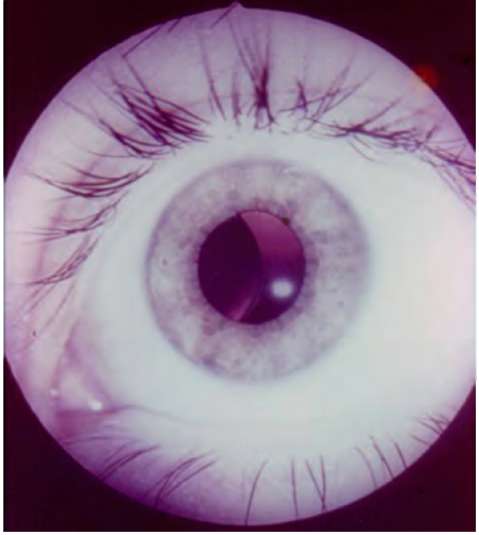

Рис. 25.1. Увеит при ревматоидном артрите